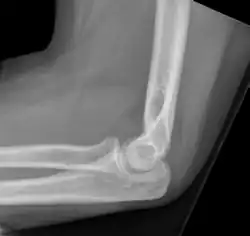

W czasie największych odkryć Wilhelma Roentgena Polska znajdowała się pod zaborami. Mimo to informacje o promieniach X dotarły bardzo szybko. Początkowo wzbudzały one wiele niepewności, jednak już wkrótce i w Polsce rozpoczęły się badania nad promieniowaniem Roentgena. Jednym z pionierów był profesor Karol Olszewski, który za pomocą rurki Plückera wykonał eksperymentalne zdjęcia przedmiotów, a w szczególności brązowy przycisk do papieru, oraz pierwsze polskie zdjęcie ludzkiej części ciała. Niespełna miesiąc później wraz ze swoim asystentem wykonał pierwsze zdjęcie ze wskazań klinicznych na którym zdiagnozowano zwichnięcie stawu łokciowego. Pierwszy polski naukowy artykuł z zakresu radiologii został opublikowany przez chirurga prof. Alfreda Obalińskiego, gdzie opisano pierwsze badanie kliniczne (zdjęcie RTG stawu łokciowego profesora Olszewskiego).

Najpowszechniej stosowana technika obrazowania struktur anatomicznych wykorzystująca promieniowanie Roentgena. Głównym jej zastosowaniem jest diagnozowanie układu kostnego człowieka.